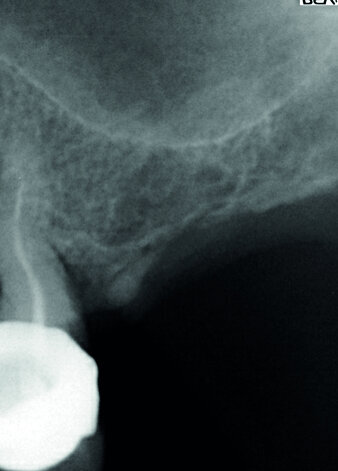

Après une séance d’ostéoactivation, pose à 45 jours d’un implant Fractal, le gain osseux obtenu à

l’apex de l’implant est bien visible à la radiographie de contrôle.

Après une séance d’ostéoactivation, pose à 45 jours d’un implant Fractal®, le gain osseux obtenu à